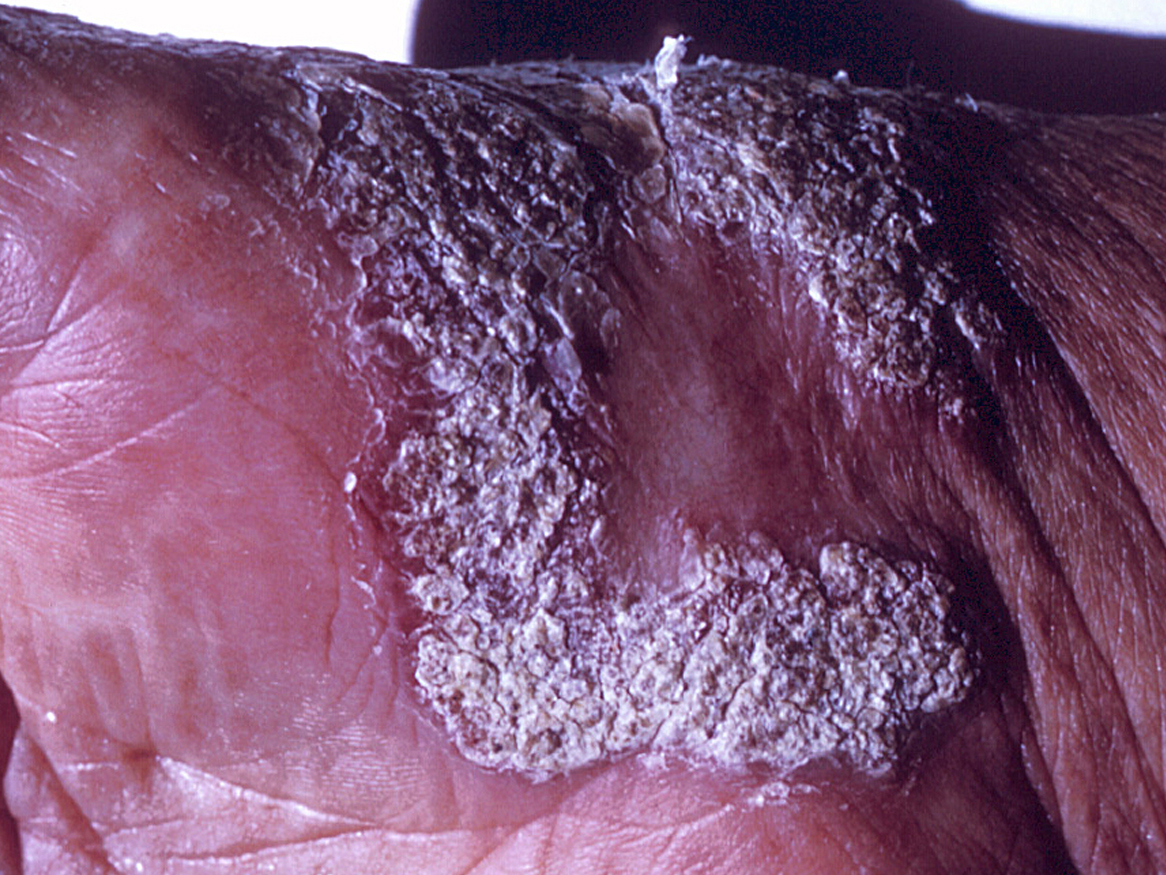

A mycotic infection of the cutaneous and subcutaneous tissues characterised by the development in tissue of dematiaceous (brown-pigmented), planate-dividing, rounded sclerotic bodies. Infections are caused by the traumatic implantation of fungal elements into the skin and are chronic, slowly progressive and localised. Tissue proliferation usually occurs around the area of inoculation producing crusted, verrucose, wart-like lesions. World-wide distribution but more common in bare footed populations living in tropical regions. Aetiological agents include various dematiaceous hyphomycetes associated with decaying vegetation or soil, especially Phialophora verrucosa, Fonsecaea spp., and Cladophialophora carrionii.

Lesions of chromoblastomycosis are most often found on exposed parts of the body and usually start a small scaly papules or nodules which are painless but may be itchy. Satellite lesions may gradually arise and as the disease develops rash-like areas enlarge and become raised irregular plaques that are often scaly or verrucose. In long standing infections, lesions may become tumorous and even cauliflower-like in appearance. Other prominent features include epithelial hyperplasia, fibrosis and microabscess formation in the epidermis. Chromoblastomycosis must be distinguished from other cutaneous fungal infections such as blastomycosis, lobomycosis, paracoccidioidomycosis and sporotrichosis. It may also mimic protothecosis, leishmaniasis, verrucose tuberculosis, certain leprous lesions and syphilis. Mycological and histopathological investigations are essential to confirm the diagnosis.

Note: tissue hyperplasia forming a white verrucoid cutaneous lesion. In Australia, chromoblastomycosis due to C. carrionii occurs mostly on the hands and arms of timber and cattle workers in humid tropical forests.